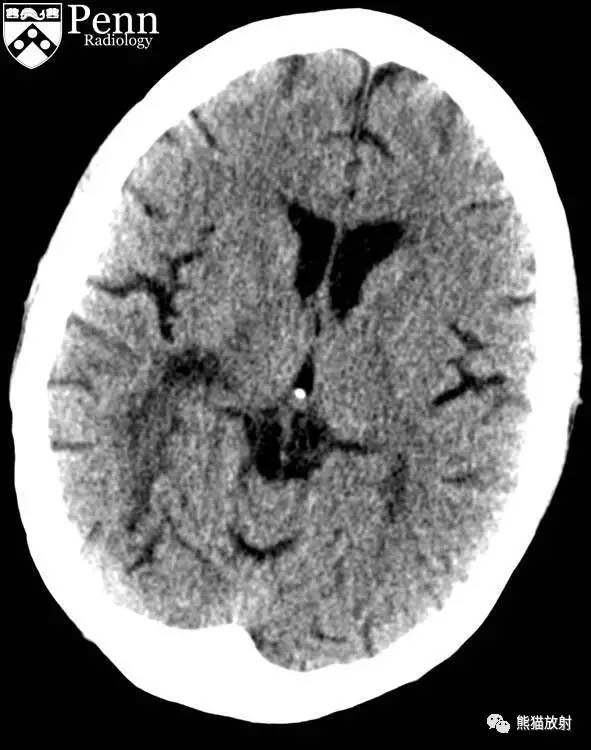

CASE 2

病史:患者男性,45 岁,进行性偏瘫,既往有酗酒、艾滋病、丙型肝炎病史。

FLAIR、DWI和 ADC图示:右侧放射冠和基底节区可见 T2 高信号病变,不伴有脑水肿,边缘部分扩散受限。

增强示病灶外缘轻度强化; MRS示 Cho 和 NAA 峰降低,脂乳酸峰值保留;免疫组化结果提示阳性染色为 JC 病毒。